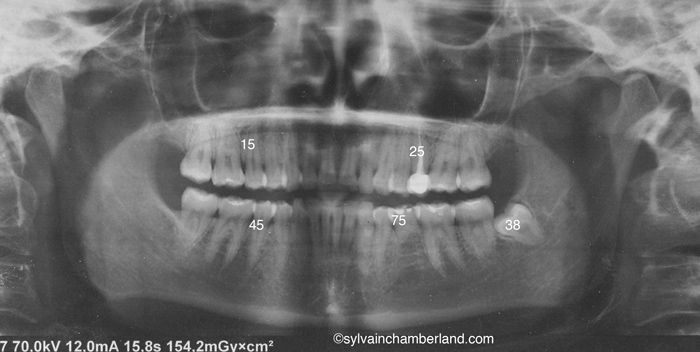

J’observe la présence de la dent primaire #75 et l’absence congénitale de la dent #35 qui devrait être en dessous. Je note un traitement de canal et une obturation extensive de la dent 25. La dent 38 est incluse. L’extraction de cette dent doit être faite au moins 6 mois avant votre chirurgie.